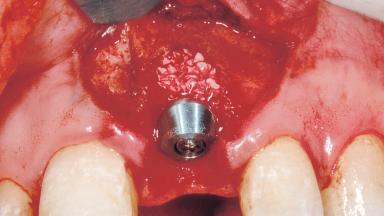

Immediate Placement of an Implant in a Maxillary Left Central Incisor Site

| Bone Augmentation | Horizontal|Simultaneous |

| Augmentation Materials | Xenogenous|Membrane |

| Placement Protocol | Immediate implant placement |

| Socket Integrity | Damage to one or more bone walls |

| Bone Volume | Damage to one or more socket walls |